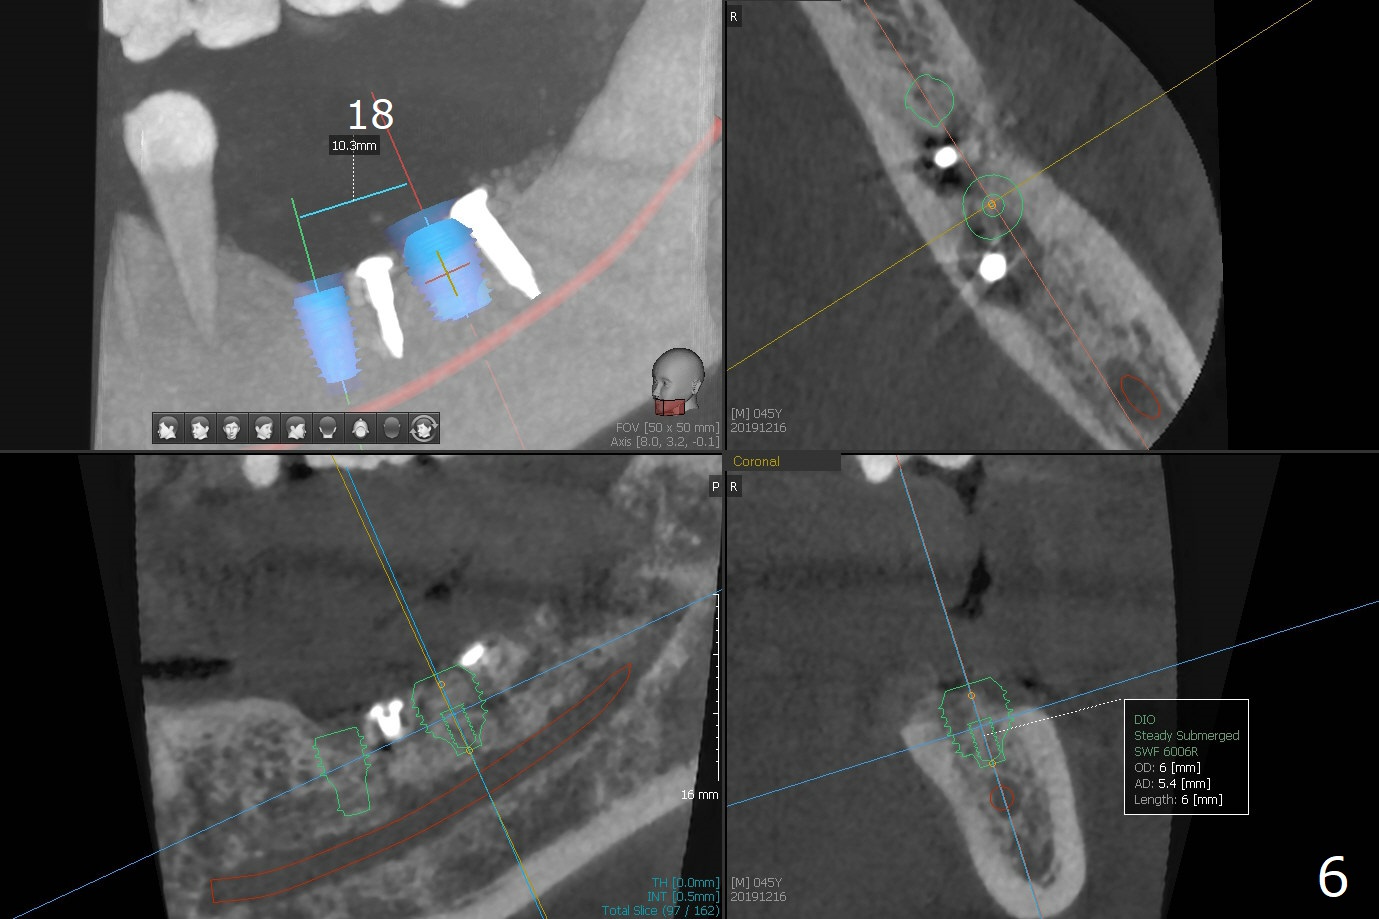

While the implant at #18 is easily removed, the one at #19 is superficial with buccal nonkeratinized gingiva (Fig.1). The latter is removed. Two small pieces of onlay graft is harvested from the left ramus and fixed in the defects with pins (Fig.2), surrounded by allograft with PRF. Since the pin at #18 looks violating the Inferior Alveolar Canal (Fig.2 C), CT is taken. In fact the pin perforates the lingual plate at #18 (Fig.4, as compared to Fig.3 (#19)). It leaves in place. Postop the wound dehisces with loss of allograft and exposure of the screws. The wound heals gradually mesiodistal with exposure of #18 screw 2.5 months postop. Follow up is disrupted by coronavirus pandemic.

It appears that short implants could be placed mesial to the original sites (Fig.5,6), 5x6 and 5x5 mm at #19 and 18, respectively, with guide as lingual as possible. The exposed buccal threads will be covered by 3-D Bond (Fig.9 white line, post decortication (red)), collagen plug and PGA suture. Healing screws are most likely used, although healing abutments should be prepared if they help wound closure.